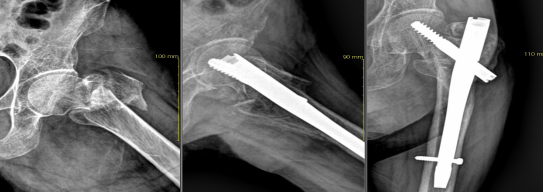

골절 및 탈구시에는 일반 방사선 촬영으로 확진하며 단순골절과 탈구의 경우에는 비수술적 치료방법으로 골절부위를 도수정복 후 석고 고정으로 치유할 수 있습니다. 그러나 도수정복 후에도 골절 부위가 이탈시 부전유합으로 진행되어 추후 어린이는 성장장애 및 외상 후 관절증을 유발시켜 장해에 이르기에 부득이 수술적 방법을 고려합니다. 본원은 최신식 이동형 C-ARM 영상장치를 이용하여 골절부위를 실시간으로 촬영하여 수술을 시행하고 있습니다.